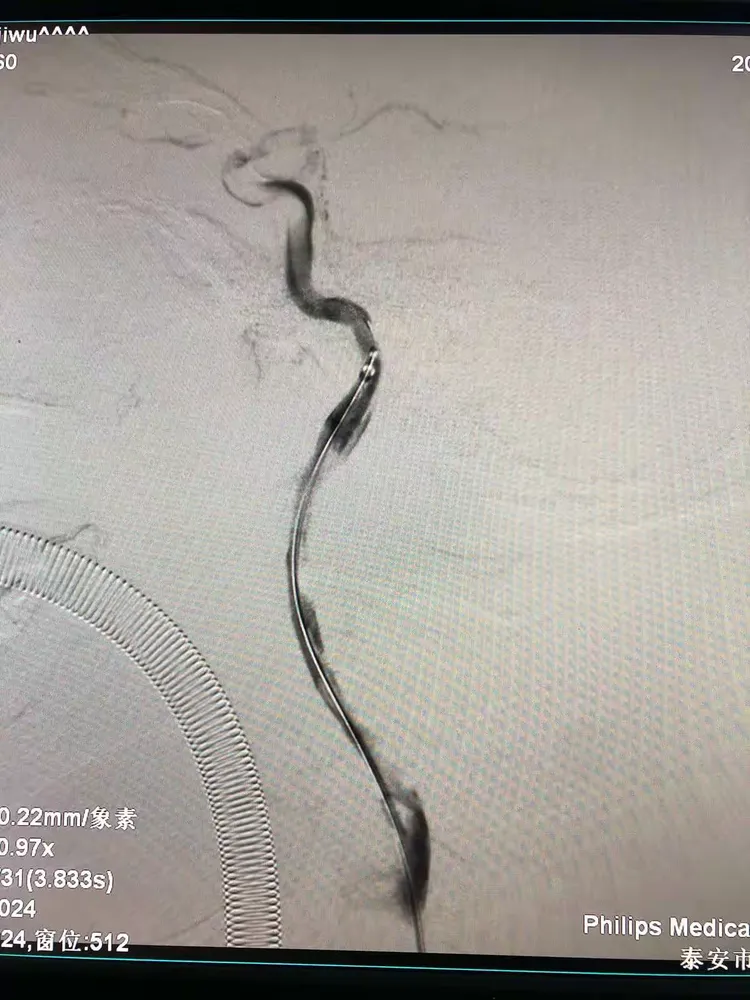

echelon 10, synchro微导丝,1:6 glubran外科胶

27通过闭塞段,将rebar-27送至右侧大脑中动脉上干